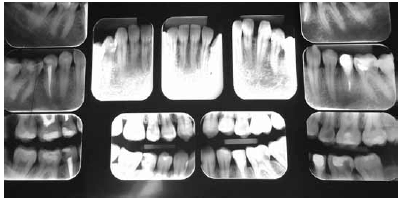

Considerando as imagens radiográficas apresentadas, de uma paciente de vinte e dois anos de idade, julgue o próximo item.

Nesse caso, o dente 24 apresenta lesão de cárie extensa.